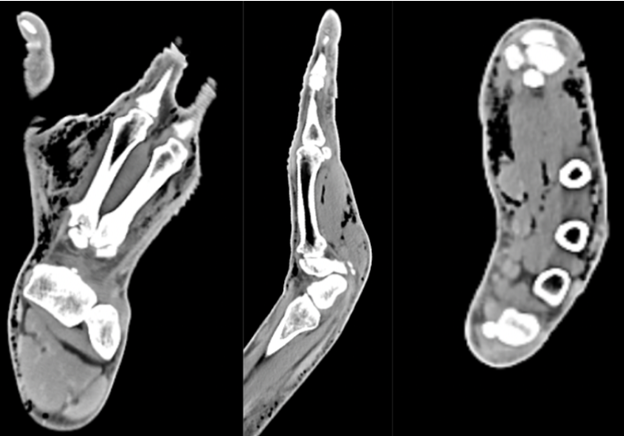

A 64-year-old right-hand-dominant male with no medical history presented with a swollen, painful right hand 10 h after a pen knife injury to the first web space. He irrigated the wound with hydrogen peroxide, but developed mild local numbness, tingling, and swelling 6 h later. He denied fever or chills. Examination revealed diffuse subcutaneous crepitus on the dorsum of the hand and forearm with intact distal sensation. Tetanus vaccination was updated. Vital signs were stable. Radiographs showed widespread SE, prompting an orthopedic consultation. The patient was admitted for observation to rule out NF. A contrast-enhanced computed tomography (CT) confirmed SE extending to the deltoid without abscess or cortical destruction (Fig. 2, 3, 4). Empiric IV antibiotics (Vancomycin, Zosyn, and Clindamycin) were initiated.

Figure 2: Computed tomography of right hand with contrast reveals no focal cortical destruction or osseous abnormality. There was moderate scattered subcutaneous emphysema diffusely through the hand.

Figure 3: Computed tomography of right forearm with contrast reveals no focal cortical destruction or osseous abnormality. There was moderate scattered subcutaneous emphysema throughout the volar aspect of the forearm.